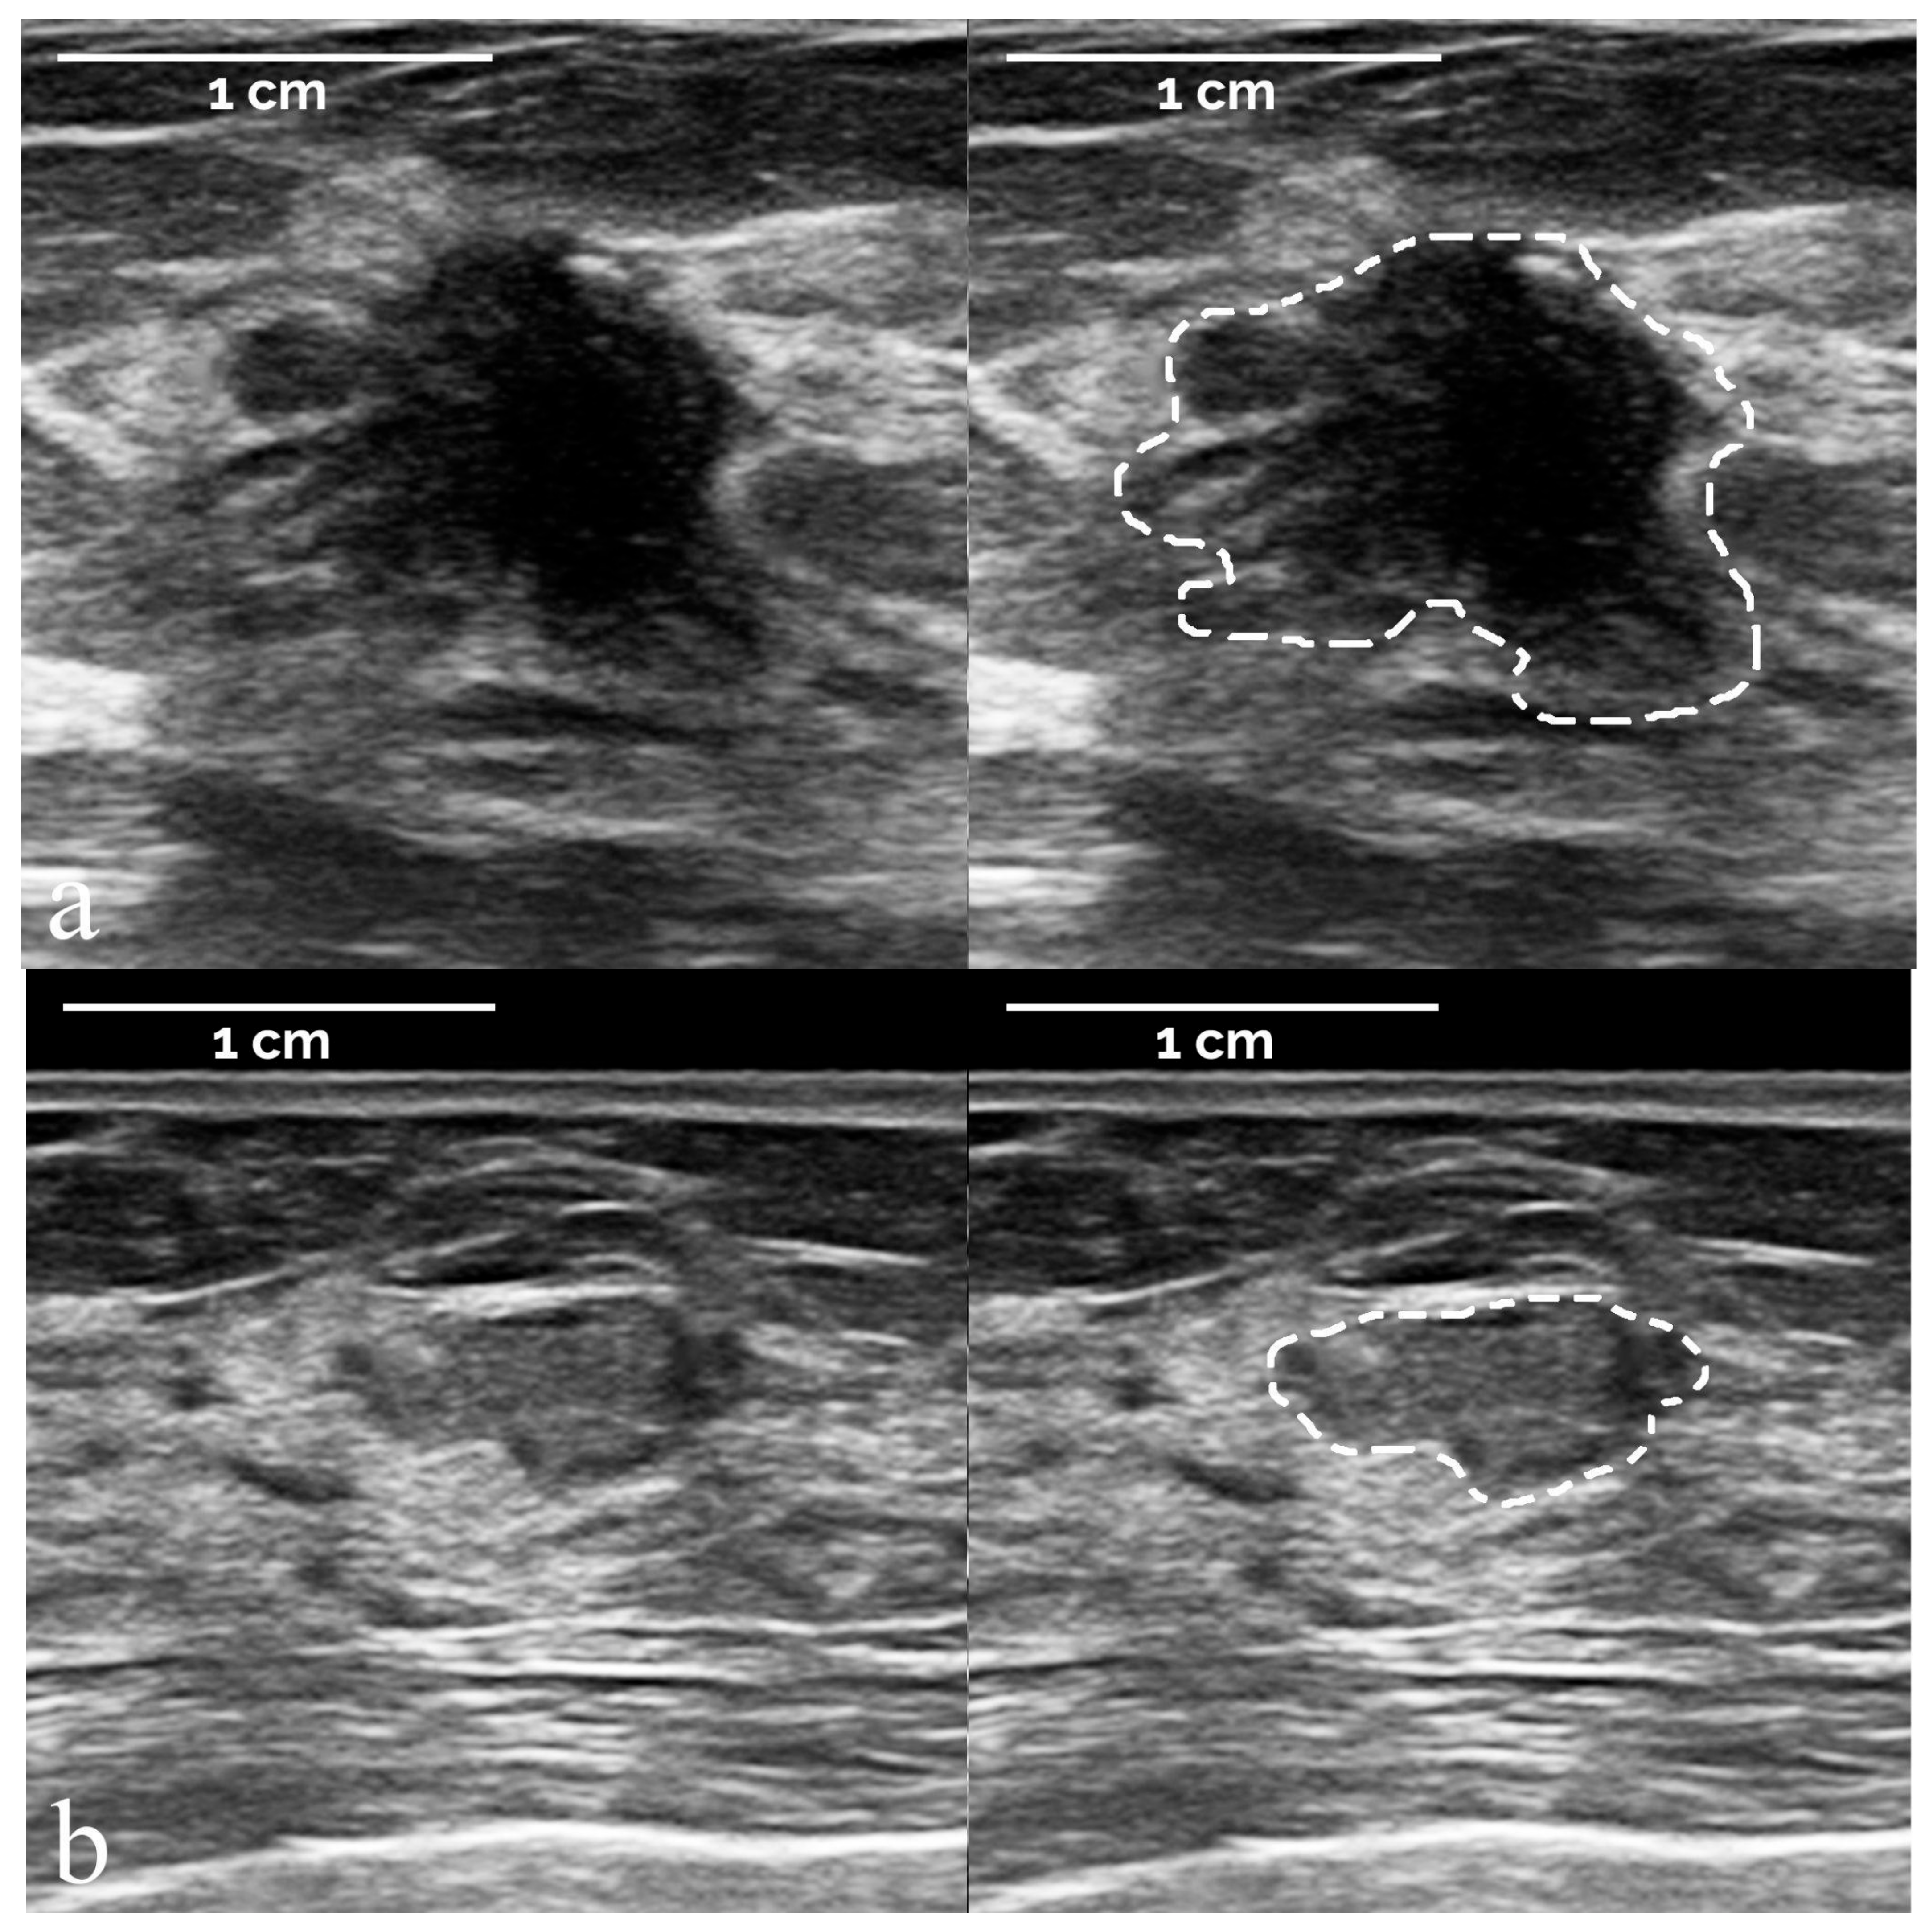

- The segmentation of suspicious masses on all 821 images was performed manually by a board-certified radiologist with 34 years of experience in breast imaging, using the TRACE4 segmentation tool. The same radiologist (at a time distance of 8 weeks) and a second board-certified radiologist with 7 years of experience independently segmented the masses on a random subsample of 50 images from the training dataset, fully blinded to histopathology and other segmentations.

3.1. Study Population and Image Sets

3.2. Radiomic-Based Machine Learning Modelling

3.3. BI-RADS Diagnostic Categories Classification